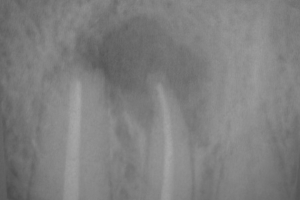

Перед операцією проводиться ретельний огляд, рентгенологічне обстеження для уточнення діагнозу та показань до хірургічного втручання. Якщо є можливість, то до операції проводиться пломбування кореневого каналу зуба, який спричинив розвиток запального процесу, до верхівки.

Під місцевою анестезією робиться доступ через ясна та кістка, відсікається верхівка кореня зуба. Також видаляється запальне вогнище та інші утворення, всі змінені тканини навколо верхівки кореня.